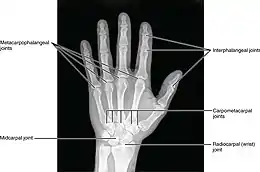

The diagnosis is based on a clinical presentation, molecular analysis, electropherogram and radiograph.[10][11][4] This disease is diagnosed within the first few years of life.[4] Identification of the main characteristics is the key factor in diagnosis. Molecular analysis is used to examine the DNA of the affected person and their parents.[10] For this, a blood sample is needed and the DNA will be extracted with an automatic DNA extractor.[10] The results will show the mutated chromosome and identify if this chromosome was passed on from a parent.[10] A radiograph will show abnormal growth plates and misshapen bones in the limbs.[7][3][10] This can confirm the abnormal development and premature fusion of the regions where the diaphyses, of certain long bones, meet their epiphyses.[4] Electropherogram is used to identify genotyping. These results can be used to compare to a normal sequence and relatives sequences.[12]